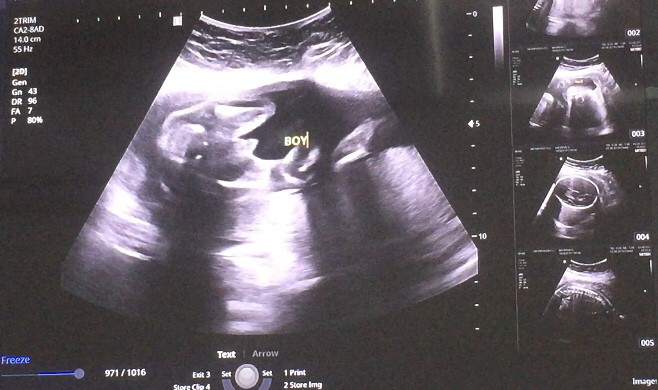

ชายจร้า

ลูกชายค่ะ

ผช จร้า

ผช.จ้าา

ผช จ้าา

ชายค่ะ

ชายจ้า